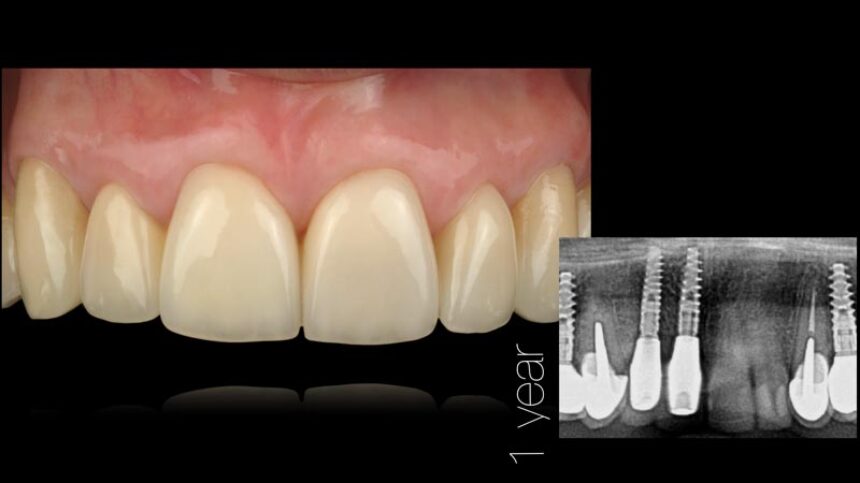

Αισθητική Οδοντιατρική με Εμφυτεύματα – βασικά επιστημονικά στοιχεία

Ανατομικοί παράγοντες με καθοριστικό ρόλο στην αισθητική αποκατάσταση επί εμφυτευμάτων – Διάγνωση και σχεδιασμός θεραπείας.

Διαχείριση μαλακών ιστών.

Χειρουργικές τεχνικές για την αύξηση των σκληρών και των μαλακών ιστών.

Μακροπρόθεσμα αποτελέσματα μετά από 30 χρόνια εμπειρίας.